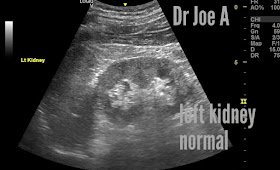

= no back pressure changes on the kidneys as yet